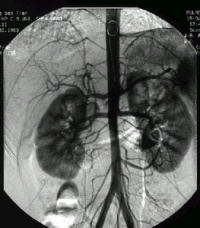

脑动脉造影[编辑 | 编辑源代码]

脑动静脉畸形有以下典型表现:①显示畸形血管。这是特征表现,呈一团管径相仿相互纠缠的迂曲扩张血管。畸形血管团的范围可小如指甲,大如手掌,多见大脑半球皮质.②异常粗大的供养动脉和引流静脉伴局部循环加快。此为局部血流短路的表现。③血流分流现象:造影剂随血流经畸形血管的短路大量流入静脉,因此,血管畸形部分因血流量增加而显影十分清楚。④血肿的表现:血管破裂出血致脑内血肿,血肿的主要表现为局部占位征象,一股脑部动静脉畸形无血肿时,脑血管不出现占位征象,脑血管不移位。

5.脑血管造影:最可靠、最重要的诊断方法,动脉期可见血管团、供血动脉及早期显现的引流静脉。

4、脑血管造影是本病最可靠和主要的诊断方法,并能行血管内介入治疗。

1、由于有多发的可能,术前应作全脑血管造影或双侧颈动脉造影,或按畸形血管部位推测,加作椎动脉造影。典型的脑动静脉畸形包括供应动脉、畸形灶及引流静脉三部分。通过造影应查清供应动脉来源及引流静脉走向,畸形灶的部位及范围,有无血肿等合并症,以及病人有无它处畸形。才能制订出完善的手术计划,也是手术成功的关键。